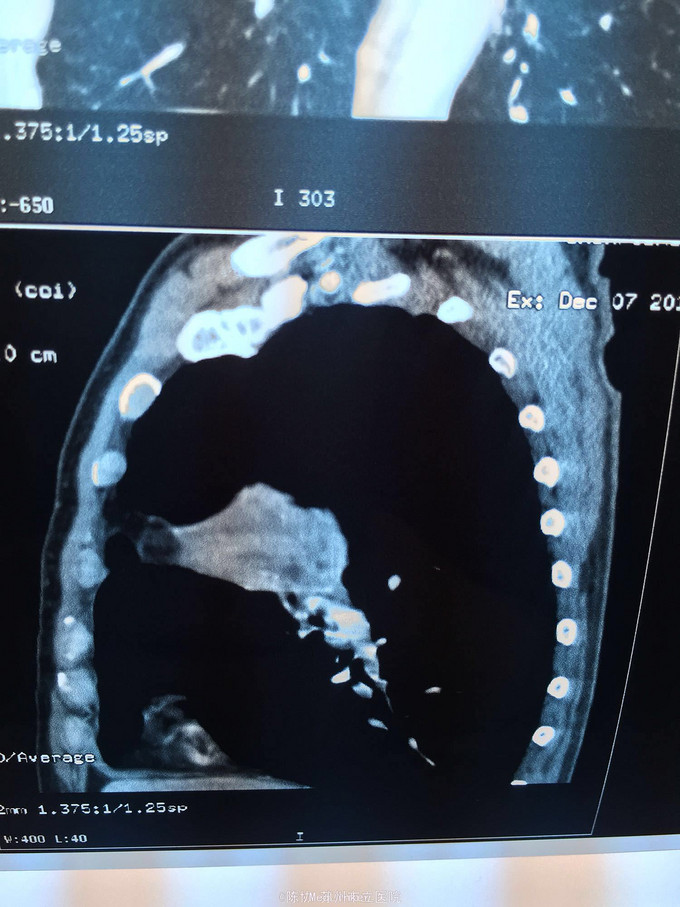

主诉:体检发现右上肺不张半月 77岁男,半月前体检发现右上肺不张,无不适。无消瘦,无咳血,无干咳。去年4月右上肺炎,抗生素治愈,当时CT未见肺肿块。入院支气管镜发现右上支气管开口组织增厚闭塞,开口近侧有隆起约3x3平方毫米,取活检5块病理示中度非典型增生。CT提示在右侧主支气管外侧有30x30平方毫米块影,压迫右上支气管开口处。三大常规和生化检查正常,肿瘤指标正常,TAP正常。

右侧中央型肺癌 重做支气管镜,精于定位找到病症组织,获得病理诊断来指导治疗。 胸外科医生不建议手术,理由是肿瘤位置靠近主支气管和气管,袖状切除不一定看干净。 请问正确的诊断,和比较合理的治疗方法是什么?求助大家思考评论